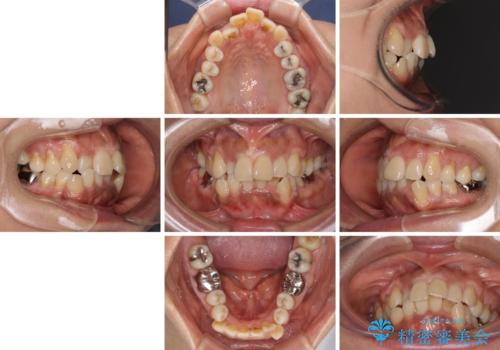

- 八重歯やクロスバイトを気にして来院された患者様です。

口元の突出感はありませんでしたが、デコボコが強く、非抜歯矯正とすると出っ歯仕上がりとなる可能性があったため、上下左右の第一小臼歯4本を抜歯し、ワイヤー装置にて矯正治療を行うこととしました。

抜歯矯正により口元が引っ込みすぎて、ほうれい線が顕著となるのではないかと心配しておりましたが、矯正後にほうれい線が気になることはなく、口元もすっきりとした感じになりました。